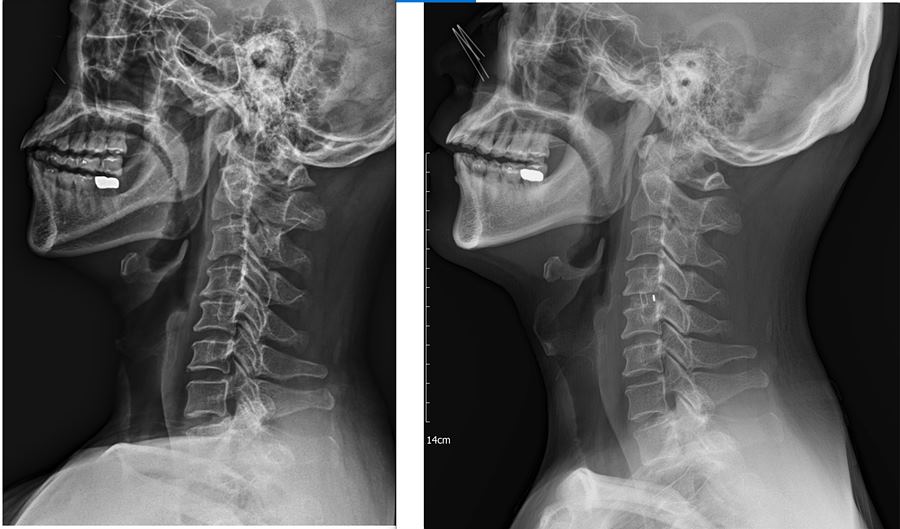

3. X-Ray 세로 사진 : 오른쪽이 수술 후

. 신경공을 더 넓히지는 못했지만 케이지를 넣음으로써 분절간 높이가 수술 전보다 확연히 높아졌다.

. 교수님도 분절 사이가 높아졌으니 그만큼 공간이 더 생겼고 크게 걱정하지 않아도 된다고 하셨다.